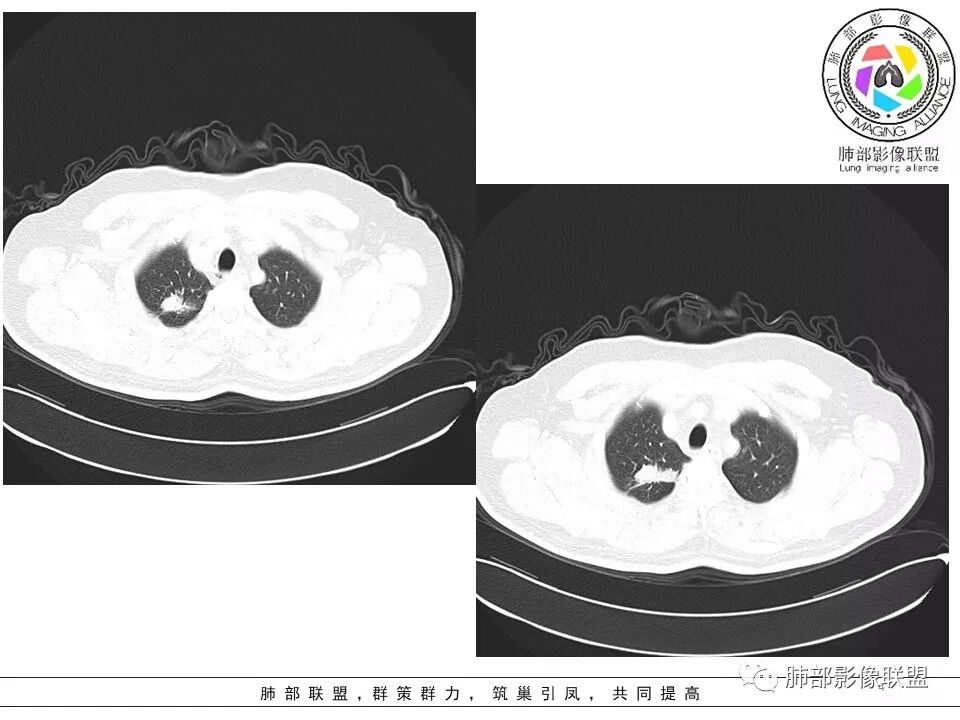

病史:男性,49岁,反复咳嗽月余,伴左胸痛;   影像:形态奇特,长毛刺,疑多灶,支气管阻塞不明显,毛刺不明显,纵膈窗密度不均,其内似见低密度,有凹陷,膨隆不除外,纵膈窗胸膜有点增厚。诊断:结核(右上肺)鉴别:不符合,无钙化,无胸腔积液;腺癌(无淋巴结)。处置:寻找结核相关检查,肿标,纤支镜,增强。

患者中年男性,主诉:咳嗽  胸痛。  胸CT:右肺上叶尖段占位,病灶位于支气管外,病灶周围部分区域可见毛玻璃影,病灶边缘不规则,部分区域可见平直,胸膜牵拉(无胸膜凹陷),柔软长毛刺,分叶,纵隔窗病灶没可见低密度区,左肺尖可见一点状病灶,病灶整体考虑良性疾病:感染性病变(结核?),感染后机化?。恶性病变待除外。

右肺上叶结节,边缘平直为主,病灶比较散,周周似乎有卫星病灶,边缘有胸膜牵拉,从粗到细,左肺尖奕有卫星灶,综合考虑结核。

晨读:患者中年男性,反复咳嗽1月余,伴左胸部疼痛1周就诊。胸部CT:右肺上叶尖后段不规则结节,见长毛刺、胸膜牵拉、条索影,周围见卫星灶。未见明显淋巴结肿大,符合结核病变。鉴别其他。但其病灶位于右肺,主诉左胸痛,是误写,还是?

一米阳光:    晨读,右上肺结节影,形态不规则,边缘平直,部分凹陷,长软毛刺,胸膜牵拉,周围卫星灶。考虑结核。鉴别腺癌,部分边缘彭隆

傅昌瑜:  男,49岁,反复咳嗽1月余,伴左侧胸痛1周。右肺上叶尖段结节,边缘平直、凹陷,周周似乎有卫星病灶,边缘有胸膜牵拉,从粗到细,左肺尖见小点状病灶,考虑良性病变,结核可能性大。

灵魂清零: 右上肺结节影既有良性征象也有恶性征象,良性:边界平直,形态扁平,左肺尖有病灶;恶性:周围边界清楚的磨玻璃影,内部密度不均匀,局部边界有膨隆!考虑腺癌,肉芽肿病变待排!进一步增强扫描!再穿刺活检检查!

小飞:  晨读:右肺上叶不规则结节灶,沿支气管走形分布,边缘平直,U型凹陷,脊柱侧有少许磨玻璃影,左肺尖少许斑点灶,综合考虑结核。

丽:  右上肺结节,有平直征、U形征,部分边缘呈膨隆,倾向于良性病变,考虑肉芽肿性病变可能。

南边:这病史,慢性或亚急性炎症,癌都可以

影像,气管憩室,两肺尖都有病灶,长索条

右肺上叶病灶两部分

纵隔窗提示内侧部分密度不够实

边缘平直、凹陷为主,部分膨隆

内部小点状影提示可能支气管腔内粘液栓

左肺尖及右肺病灶附近见小斑点,边界尚清

遗憾的是:层厚太厚,无重建

这些是否是边界清楚GGO?

1、病灶整体形态不是类圆形,边缘凹陷、平直为主,长轴重建可能更明显,长索条,附近卫星灶,左肺尖有类似小高密度影;按常规:首先要考虑结核

南边:2、不踏实的地方:GGO是不是容积效应所致?如果薄层,边界清楚GGO,就考虑继发瘢痕癌

因此我们需要的是:薄层、重建,看GGO边缘、看整体形态